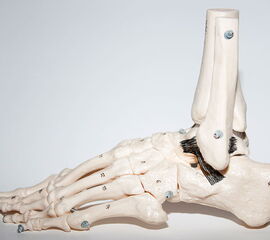

Die knöcherne Malleolengabel wird von Tibia und Fibula gebildet, die beiden Knochen werden durch die vorderen und hinteren Syndesmosenbänder, sowie die Membrana interossea stabilisiert. Der am häufigsten verletzte laterale Bandkomplex besteht aus dem Ligamentum talofibulare anterius (LTFA), dem Ligamentum fibulocalcaneare (LFC) und dem Ligamentum talofibulare posterius (LFTP) zusammen. Der typische Unfallmechanismus ist die forcierte Plantarflexion und Inversion des Sprunggelenks 7. Das LFTA ist das schwächste der drei Außenbänder und wird am häufigsten verletzt 8. Das LFTA limitiert die Plantarflexion und die Innenrotation 9. Das LFC ist 2-3,5-mal stabiler als das LFTA. In etwa 25 % der Fälle treten kombinierte Läsionen des LFTA und des LFC auf.